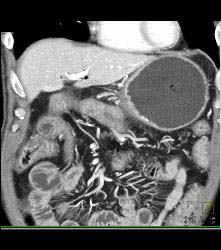

Gastric Outlet Onstruction to Tumor